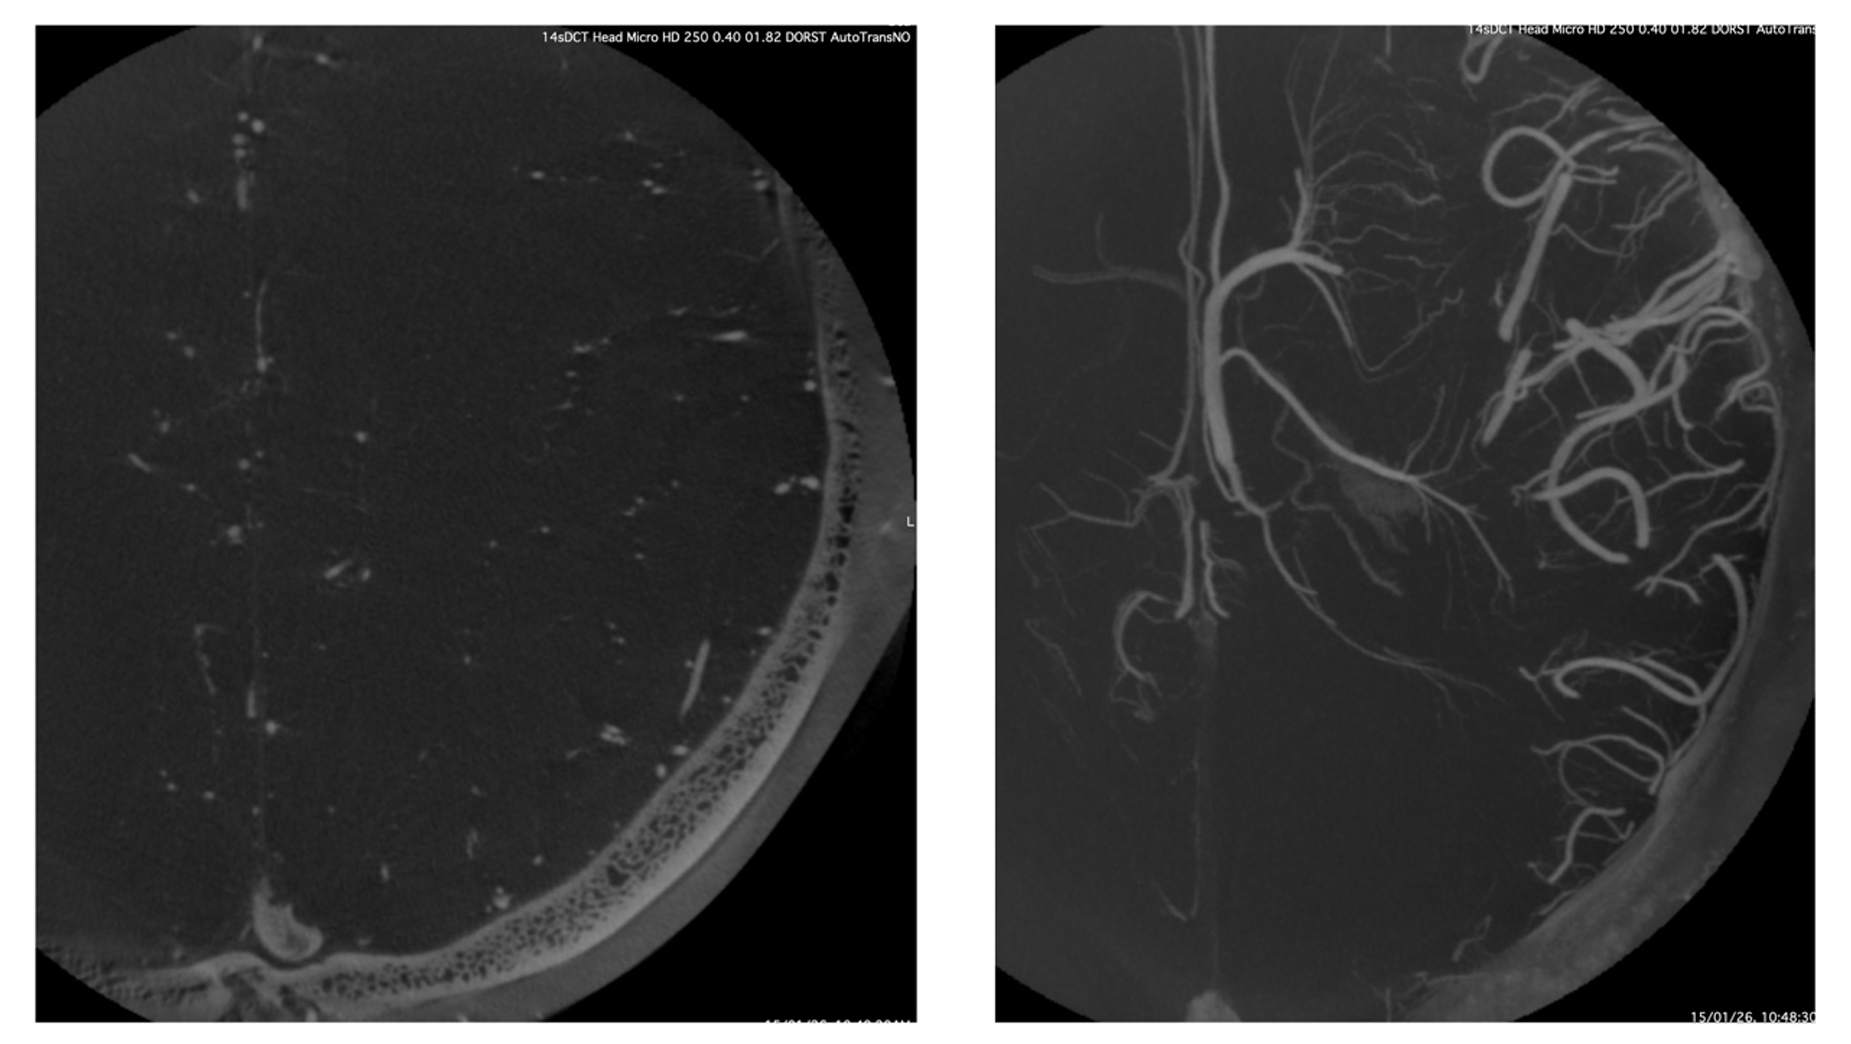

This example shows the typically smaller FOV that is explored by this technique. One can appreciate the unsubtracted source axial image with the smaller vessels seen very well in the depths of the white mater, although only half of the hemisphere is fitting into the FOV. The right-hand panel shows the MIP reconstruction of the same source image showing the massive details of the deep venous system in exquisite detail. One basic principle of this technique is a complete opacification of the arterio-capillary-venous system throughout the rotation to ensure uniformity in the imaging. Therefore, this technique does not have temporal resolution, i.e., it is not able to tell us what is artery and what is vein, but the spatial resolution is massive.